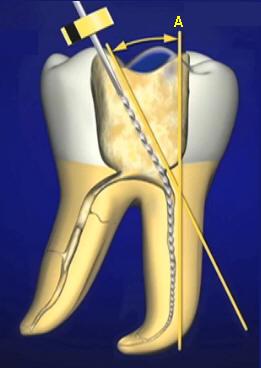

La cabeza

cortante está conectada al vástago por un

fino y largo cuello. Está numerado del 1 al

6 mediante marcas en el tallo del

instrumento. Se utilizan para la ampliación

y conformación de los conductos después del

limado seriado y ensanchamiento con limas,

en sus tercios cervical y a veces hasta el

tercio medio. Ver imagen derecha